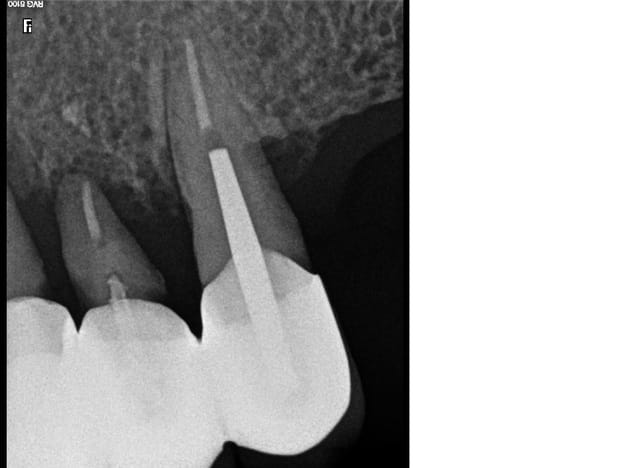

Ra 13 11 ji5dei - Eugenol